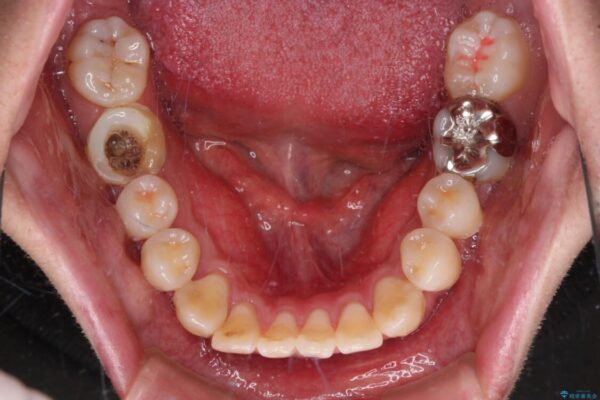

治療前

• 口元の突出感を改善!目立ちにくいワイヤー矯正で自信を持てる自然な横顔に 治療前画像